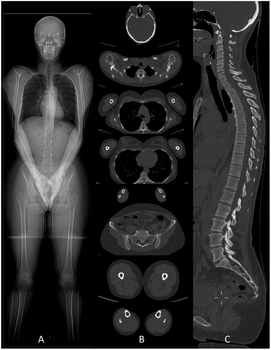

• Auto uploaded image

Actualité

Plus 1000 patients pris en charge dans notre nouvelle salle d’artériographie !